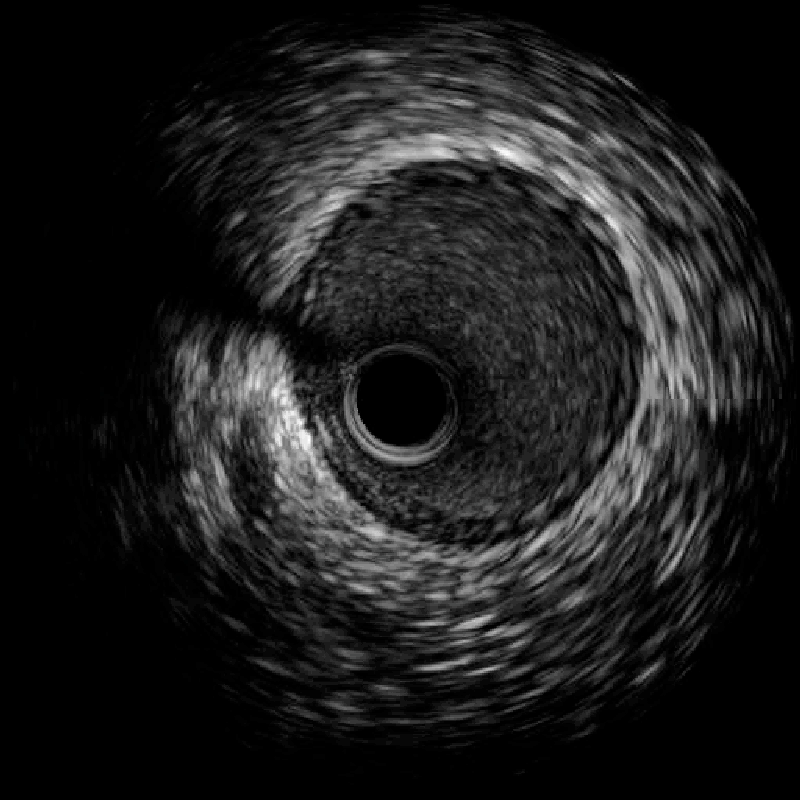

2024年10月的某天,患者程某某因胸闷两天,前来惠州市中心人民医院中文博彩平台分院(中文博彩平台人民医院)心血管内科就诊。经诊查,诊断为冠心病、急性非ST段抬高型心肌梗死 KillipI级,GRACE评分122分,危险分层高危。行冠脉造影示回旋支远段近端见大量血栓影、狭窄90%,远段远端见大量血栓影、狭窄100%闭塞,前向血流TIMI0级(图1)。心血管内科团队予为患者行PTCA和血栓抽吸术,复查造影显示:回旋支远段近端血栓无变化,远段远端血栓消失(图2)。考虑血栓负荷重,回旋支远段近端暂不宜行支架置入术,拟给予抗栓治疗后择期复查冠脉造影。

(图1)